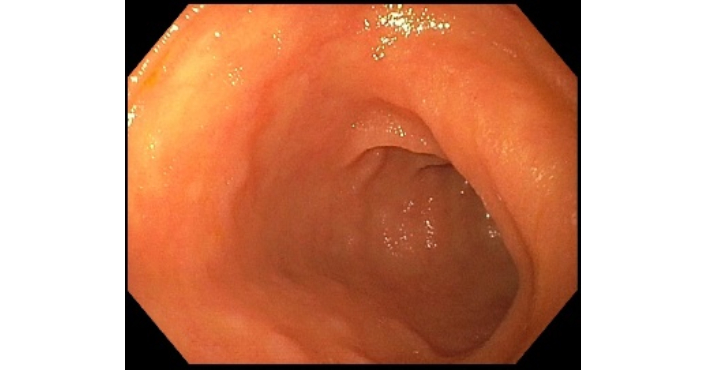

Repeat flexible sigmoidoscopy performed 3 months after short-chain fatty acid enemas demonstrated an overall normal-appearing left colon (Figure 10). Histopathological examination of biopsies from the left colon and rectum showed no acute or chronic colitis, no granulomas, and minimal crypt architectural distortion (Figure 11). Overall, this reflected the complete resolution of disease activity, consistent with clinical, endoscopic, and histologic remission. There were notable improvements in HGB 13.1 g/dL, ESR 21 mm/hr, and CRP < 0.30 mg/dL. Because her PsA diagnosis was uncertain and the presentation favored CD induced by an IL-17i rather than primary severe, penetrating Crohn’s, we recommended conservative management without advanced therapy. We also advised referral to a new rheumatologist to re-evaluate the PsA diagnosis.

Flexible sigmoidoscopy showing a normal-appearing rectum with several (4) post-biopsy scars from prior endoscopic evaluation.